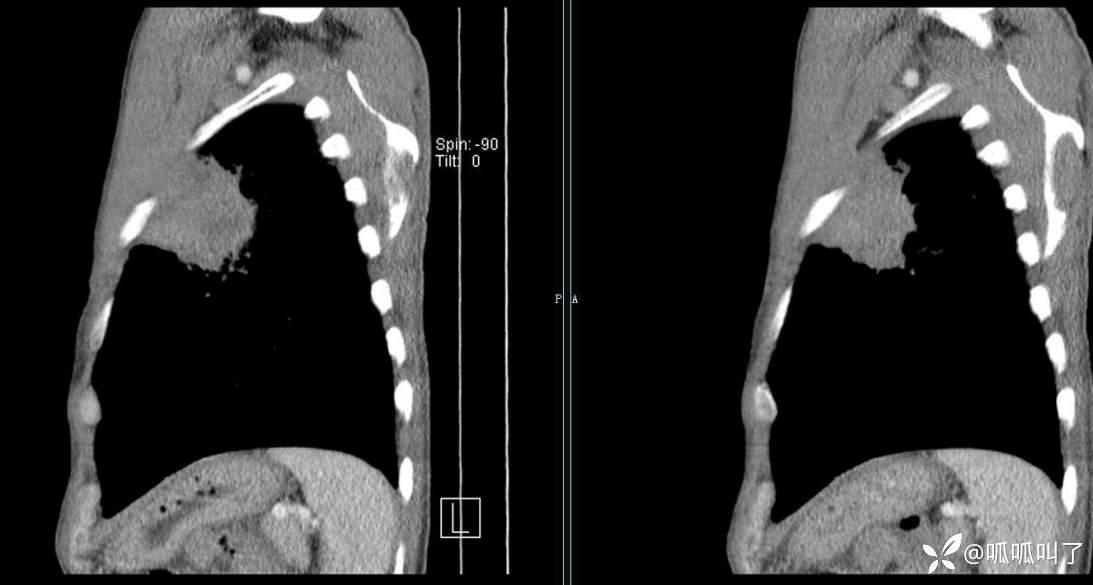

胸部CT平扫和增强: